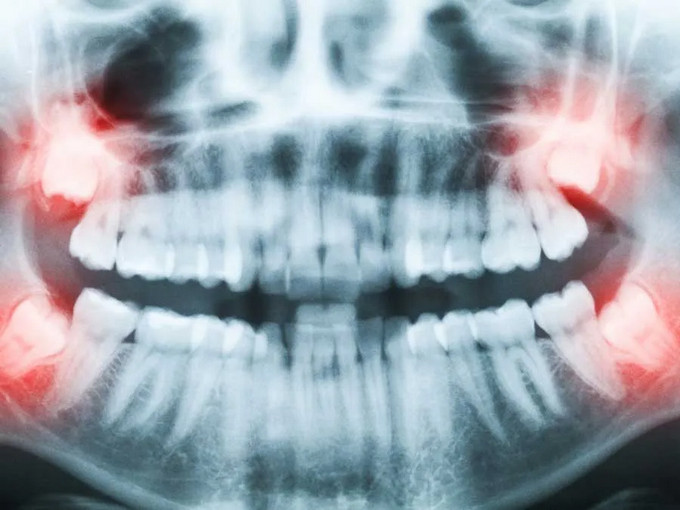

智齿通常在18~25岁萌出。因为颌骨空间不足、牙胚位置异常或角度不正,智齿长不出来,斜着或横着长,被牙龈或骨头部分或完全覆盖,就称为埋伏(阻生)智齿。这类智齿与口腔之间常形成难以清洁的“盲袋”,为细菌聚集提供条件。

4. 形成囊肿或出现占位:影像可见病灶扩大、骨质被吸收。